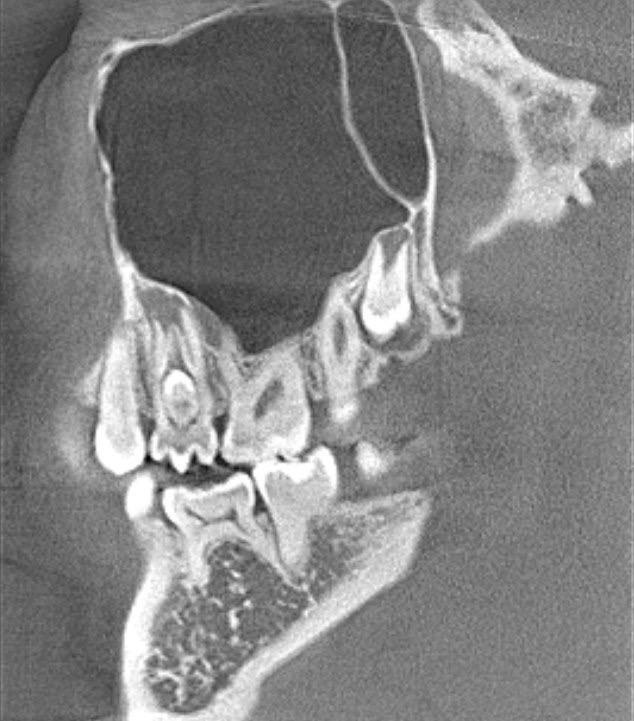

Есть такое редкое строение зуба (Dens invaginatus), когда внутри зуба как-бы находится другой зуб. Многие стоматологи только в учебниках о таком читали. Еще до того, как зуб прошел кальцификацию, его эмаль и дентин сворачиваются внутрь, образуя как бы зуб в зубе.

зуб в зубе - редкое аномальное строение зубов на КТ

Нашему стоматологу-эндодонтисту Виктории Леонидовне Ушаковой повезло уже дважды встретиться с такими зубами на практике. Оба пациента обратились с болью в зубе. По КТ зубов имелась киста у корня, нужно было лечить каналы, чтобы устранить кисту. Но во многих клиниках зубы с кистой предлагают просто удалить.